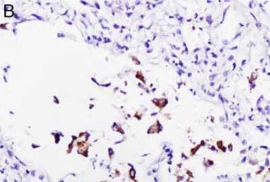

检测肺部组织中的SARS-CoV-2

|

|

|

|

检测SARS-CoV-2 RNA。A和B分别为使用竞品和Enzo探针在COVID-19肺炎样品中进行SARS-CoV-2 RNA原位杂交。竞品探针还会标记巨噬细胞(图A中圆圈部分)。

Nuovo GJ et Al. Appl Immunohistochem Mol Morphol. 2022 Feb 1;30(2):83-90.